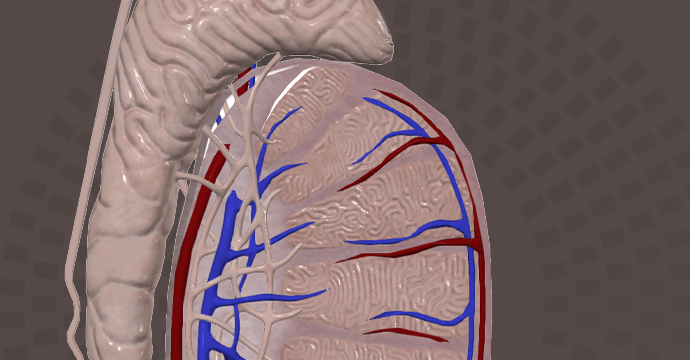

Take your understanding of human anatomy to the next level. Our comprehensive resources combine detailed information and stunning illustrations!

Enhance your studies for a truly dynamic learning experience. Explore interactive anatomy models from Complete Anatomy. Start mastering anatomy today with our free anatomy flashcards designed for quick review on the go.